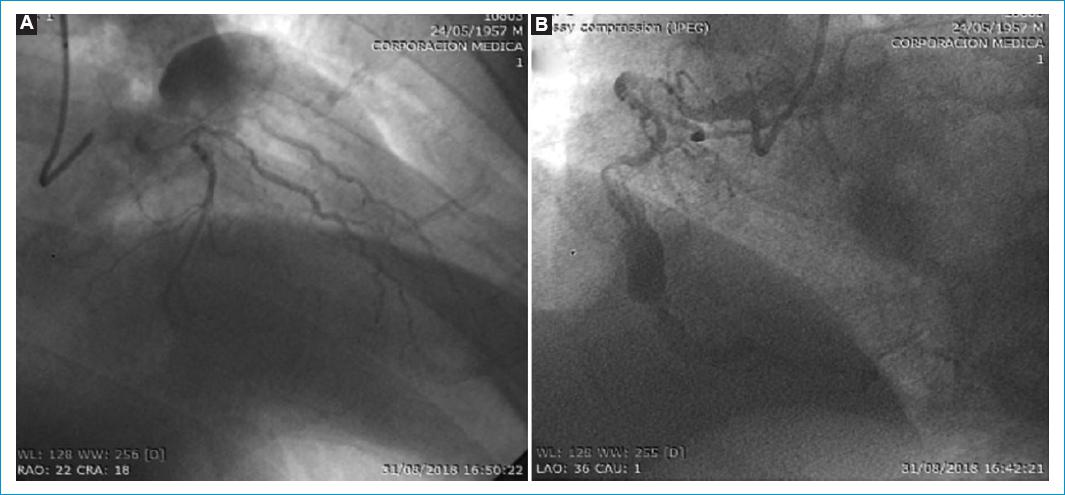

Se describe el caso de un hombre de 61 años, con antecedentes de hipertensión arterial, sobrepeso e historia familiar de muerte súbita, quien acudió al servicio de Urgencias debido a un dolor intenso en la región precordial que se irradiaba hacia el miembro superior derecho. Los hallazgos en el electrocardiograma de ingreso revelaronn un supradesnivel del segmento ST en las derivaciones V1 a V3, así como ondas T simétricas y picudas en las derivaciones V2-V6. Además, el ecocardiograma mostró hipocinesia aguda ínfero-posterior de base a punta, hipocinesia septal medial anterior y fracción de eyección del 35%. Los niveles de troponina I ultrasensible también estaban considerablemente elevados. Fue tratado con aspirina, ticagrelor e infusión de heparina, y posteriormente desarrolló un cuadro de hipotensión asociado a choque cardiogénico, que se controló con inotrópicos y vasoactivos. La coronariografía reveló oclusión trombosada en la arteria descendente anterior a nivel proximal, con lesión aneurismática de 30 x 25 mm, así como lesión crítica proximal y dilatación aneurismática de 21 x 19 mm en la arteria coronaria derecha (Fig. 1). Ante estos hallazgos, se decidió llevar a cirugía de revascularización miocárdica utilizando la técnica «on-pump beating-heart», en la cual se realiza un puente mamario izquierdo a la arteria descendente anterior, un injerto venoso a la arteria circunfleja y otro injerto venoso a la arteria descendente posterior. Previo a la cirugía, se implantó un balón de contrapulsación intraaórtico, el cual se retiró al día siguiente de la intervención.

Figura 1 A: se observa en la región de la coronaria descendente anterior a nivel proximal una lesión aneurismática trombosada de 30 x 25 mm. B: Además, se evidencia lesión proximal con dilatación aneurismática de 21 x 19 mm en la arteria coronaria derecha.